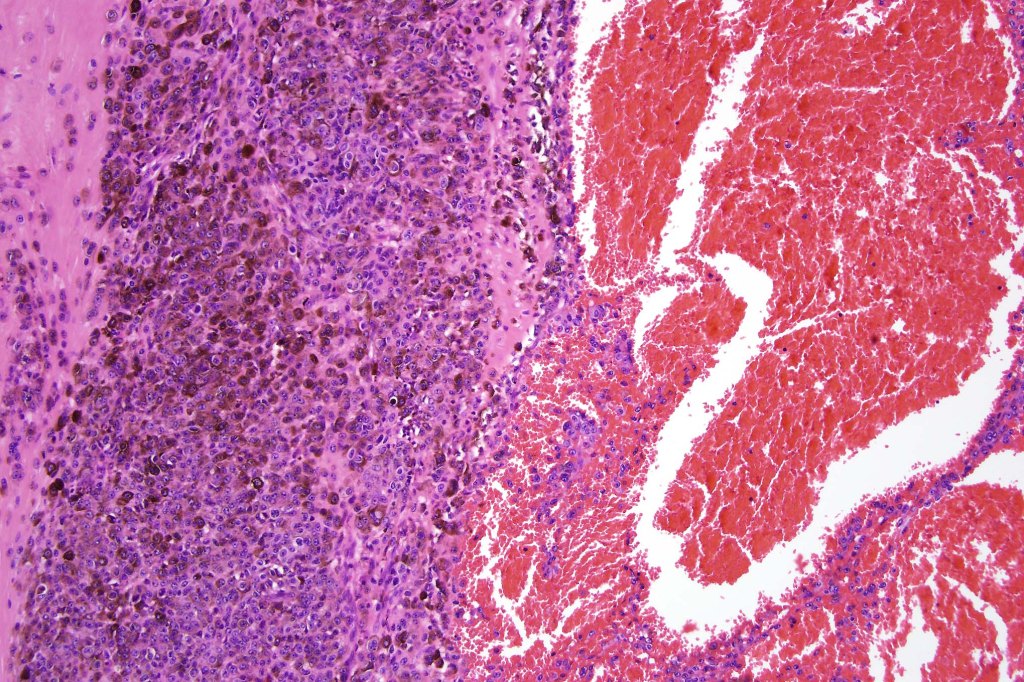

This melanoma arose in a small congenital nevus of the scalp. It metastasized widely. Varying features in different fields.